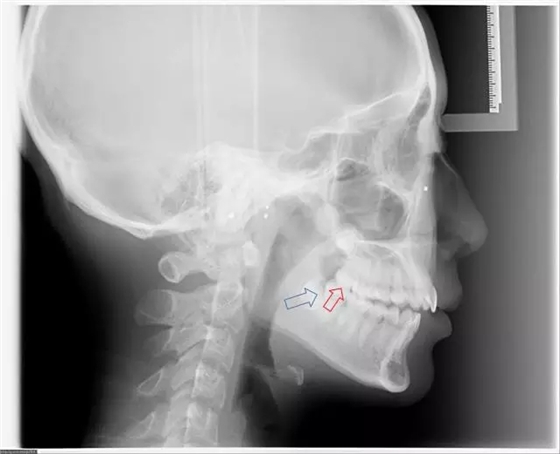

完全埋在牙槽骨里的下頜智齒,它本身倒是不出問(wèn)題。但是這些近中或水平阻生的智齒,會(huì)推擠下頜第二磨牙,導(dǎo)致第二磨牙伸長(zhǎng):

然后,第二磨牙造成咬合干擾、早接觸,前牙開(kāi) 牙合…………

甚至髁突吸收:

所以,這種智齒也還是要拔掉。